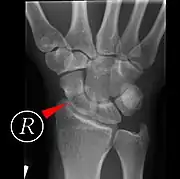

Scaphoid fracture before and after operation

Fractures of the scaphoid are the most common of the carpal bone injuries, because of its connections with the two rows of carpal bones.[1]:177

The scaphoid can be slow to heal because of the limited circulation to the bone. Fractures of the scaphoid must be recognized and treated quickly, as prompt treatment by immobilization or surgical fixation increases the likelihood of the bone healing in anatomic alignment, thus avoiding mal-union or non-union.[6] Delays may compromise healing. Failure of the fracture to heal ("non-union") will lead to post-traumatic osteoarthritis of the carpus.[1]:189 One reason for this is because of the "tenuous" blood supply to the proximal segment.[3] Even rapidly immobilized fractures may require surgical treatment, including use of a headless compression screw such as the Herbert screw to bind the two halves together.

Healing of the fracture with a non-anatomic deformity (frequently, a volar flexed "humpback") can also lead to post-traumatic arthritis. Non-unions can result in loss of blood supply to the proximal pole, which can result in avascular necrosis of the proximal segment.

Scaphoid fractures may be difficult to diagnose via plain x-ray. A repeat x-ray may be required at a later date, as might cross-sectional imaging via MRI or CT scan.[6]